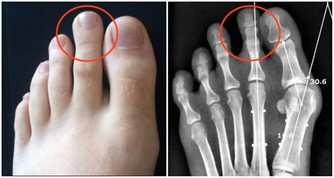

2.耳垂皺褶

在家照鏡子時可以多留意自己的耳垂,

如果發現耳垂出現了對角型摺痕,建議及時到醫院查一下心臟和血管。

耳垂皺褶和心髒病間的關係,凡死于冠心病者,耳垂皮膚幾乎都有一條皺紋。

這道耳垂皺褶在我們國家也稱為冠心溝、腦動脈硬化耳褶徵。